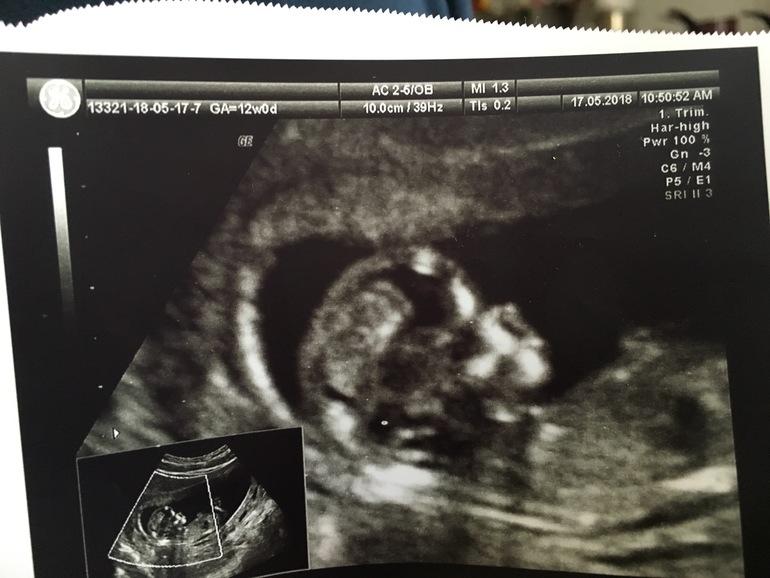

Первый скрининг

Вторая беременностьВ четверг сходили на первый скрининг. Как всегда волновалась, а вышла счастливая - счастливая. Записываю для истории :

КТР 61,3 мм

ТВП: 1,3

Малыш прикреплен по задней стенке. Говорят, похоже на девочку. Но я пока стараюсь об этом не думать. Узнаем через пару недель.

"Размер обуви " 10,03 мм)))

Опережает на 4 дня срок, все замечательно, никаких отклонений нет. Врач еле-еле смогла "поймать" и измерить ТВП, потому что ребёнок все время крутился, играл с ножками и ручками. И ротик так мило открывал. А когда папу позвали, сразу уснул)))

По крови тоже все отлично, все риски 1:100000